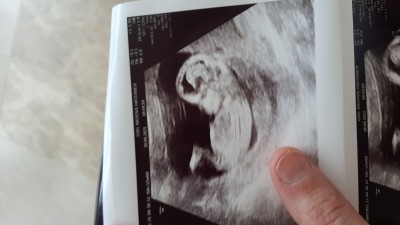

sizce bebegimizin cinsiyeti ne cok merak ediyorum 12 haftalik doktor cinsiyetini göremedi

Kapatılma nedeni: Cinsiyet tahminlerini sol üst köşeden konu dışı sohbetten sorabilirsiniz